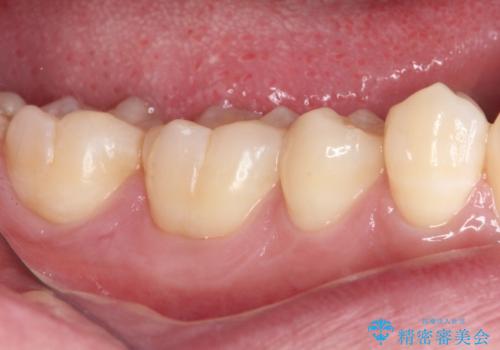

- 右下の奥歯が噛んだ時に痛み、冷たいものがしみることを主訴として来院された患者様です。

精査の結果、歯が欠けていてその下に虫歯が認められました。

また、咬合面(歯の噛む面)に以前治療した樹脂の詰め物があるため、一度外して虫歯を完全に除去し、

精度の高いセラミックインレーにて修復処置することとしました。

噛んだ時の痛みや、冷たいものがしみる症状はなくなり、見た目も自然でどこが詰め物かわからないと、患者様は大変満足されました。